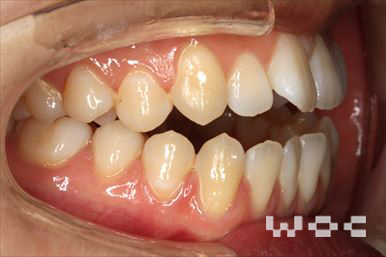

出っ歯エッジワイズ装置

特に装置の希望はなかったので、エッジワイズ装置を選択。

歯の移動量が大きいので歯根吸収の可能性がありましたが、目立った吸収は見られませんでした。-

- 年齢:17歳女性

- 主訴:出っ歯、前歯のガタガタが気になる

- 基本矯正料金:78万円

- 治療期間:1年2ヶ月

- 抜歯部位:上顎両側第一小臼歯